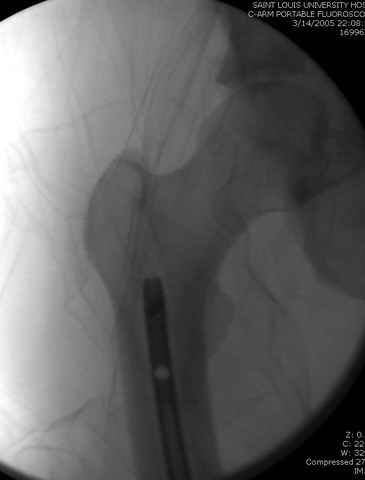

03.14.2005

больному 42, автоавария, политравма, открытая черепномозговая травма, безсознании, открытый перелом бедра, размозжение мягких тканей, дефект кожи на передней поверхности бедра около 13 см2 от ожога, компартмент синдром.

По поводу открытого перелома больной ургентно взят на ретроградное интрамедулярное штифтование, после рутинного дебрайдмента и фасциотомии на бедре и на голени.

перелом бедра

интраоперационные